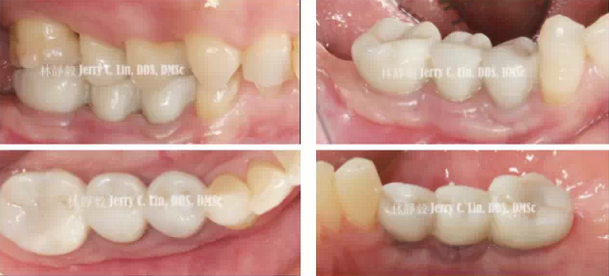

嚴(yán)重種植體周圍炎的處理(二)——林靜毅醫(yī)師